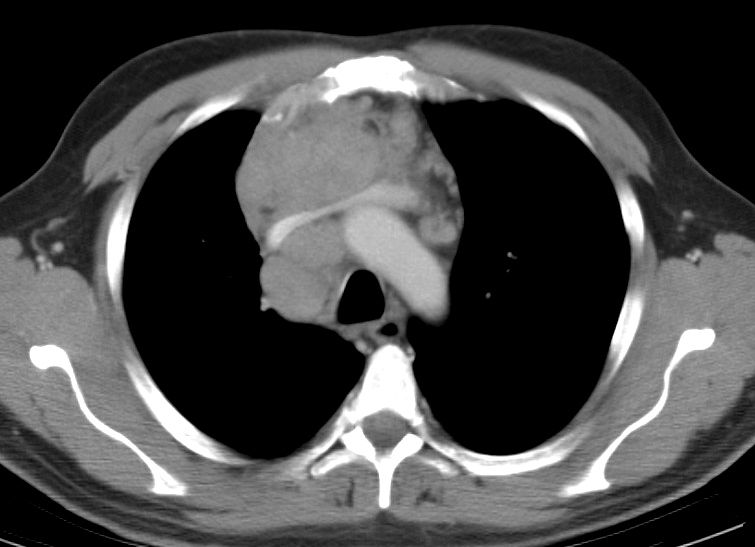

Gallery Mediastinum Lymphoma 10c

10c